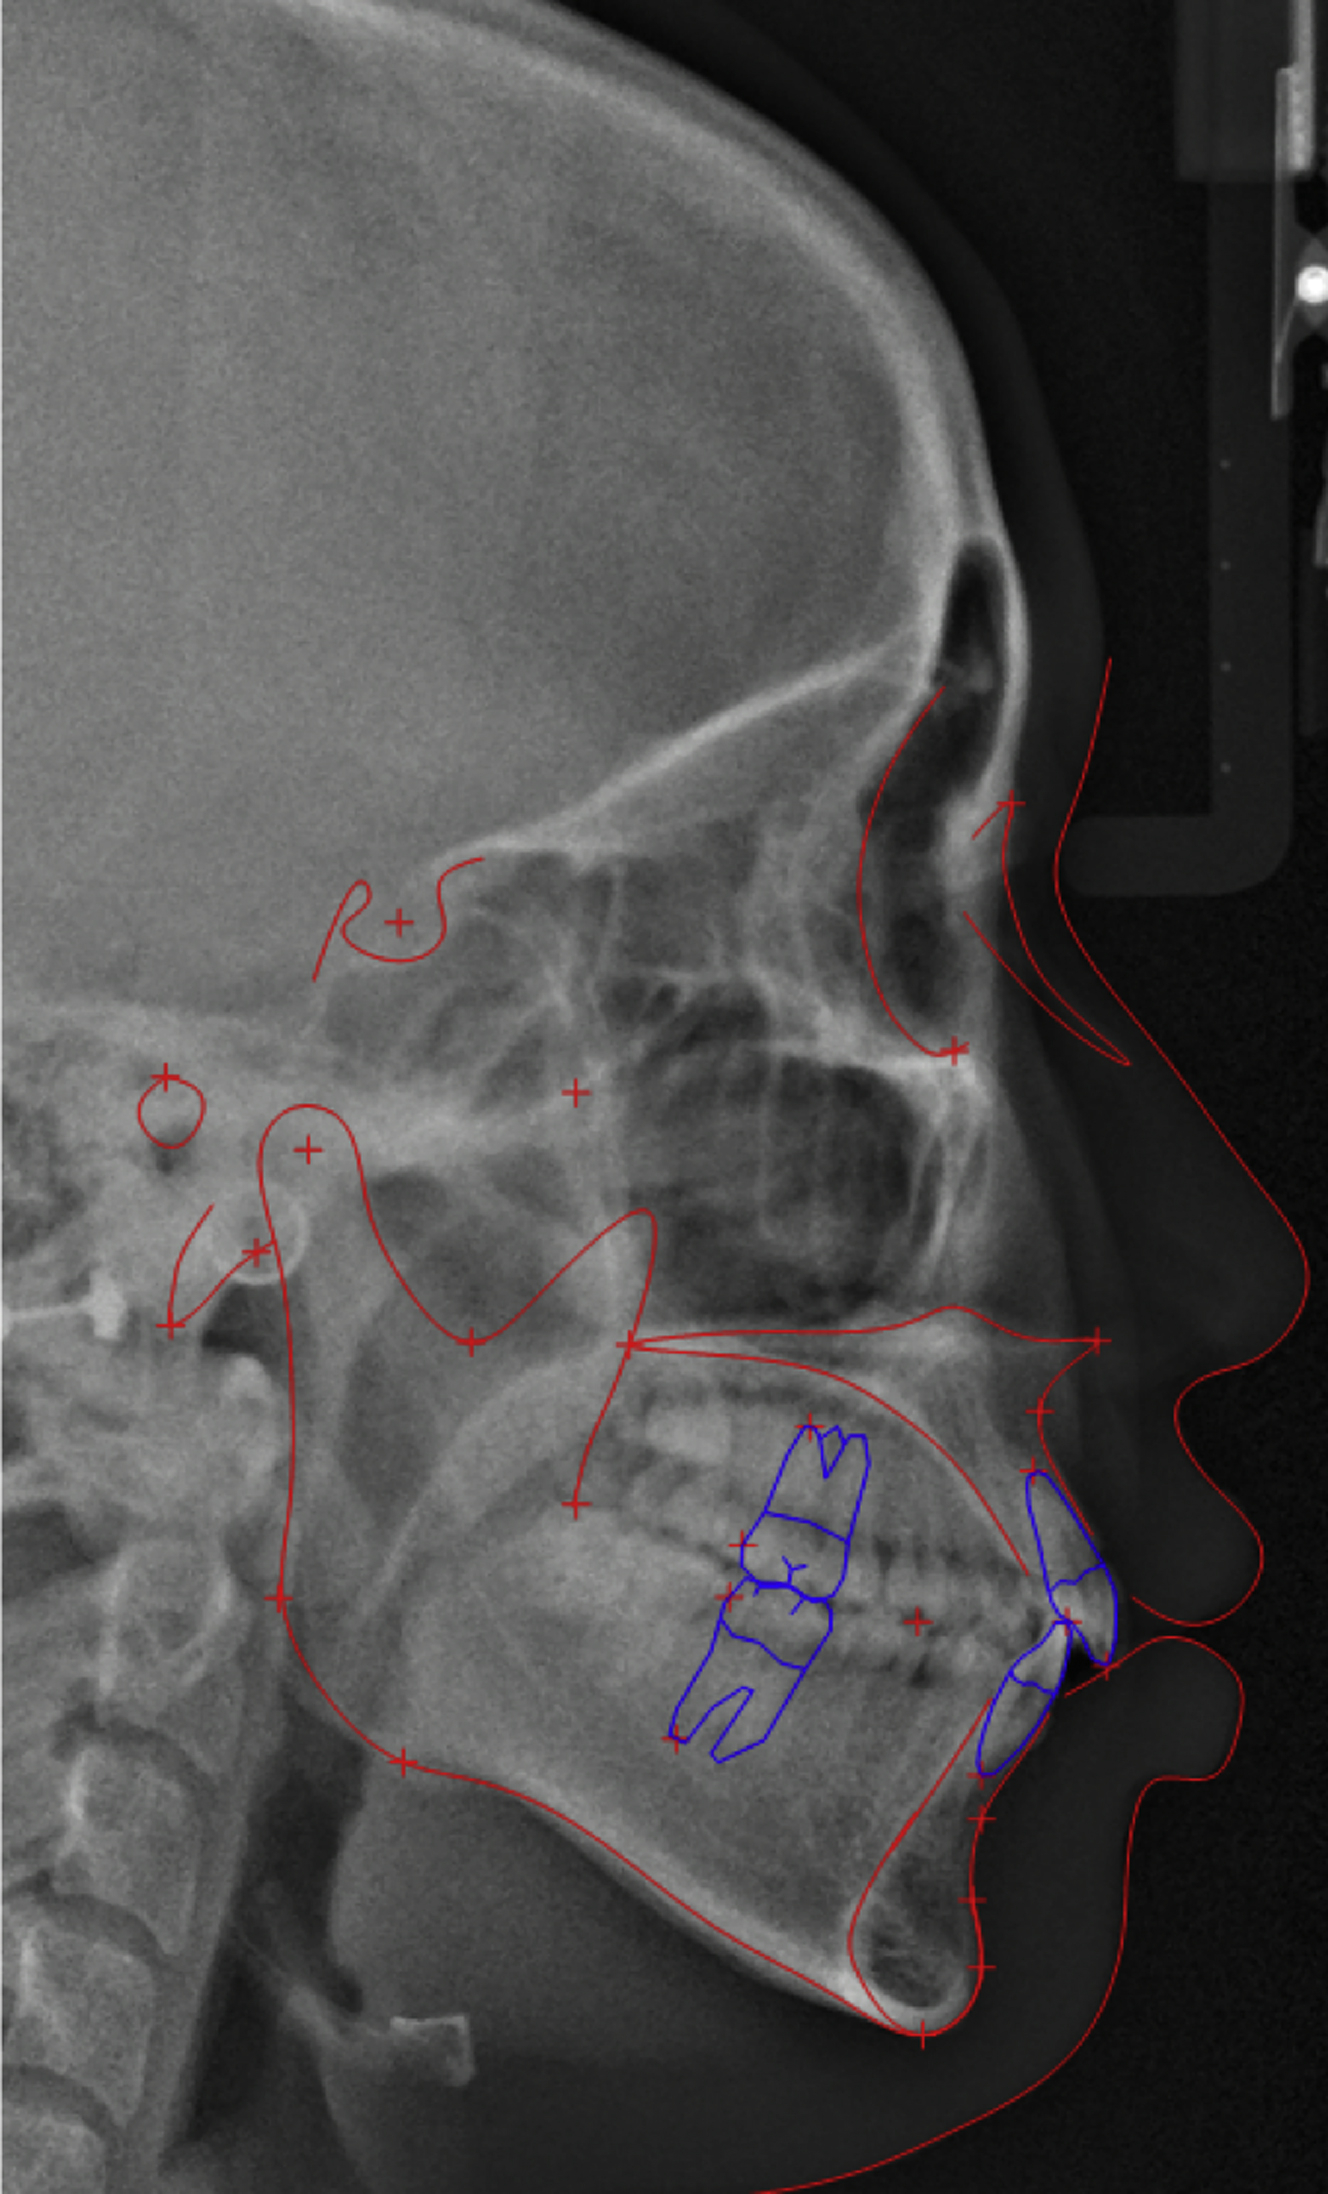

The lateral cephalogram is the method used most commonly to analyze the malocclusion. Anatomic landmarks are identified, and linear and angular measurements are used to analyze the patient’s malocclusion ( Fig. 1 ). The measurement values are compared with the norm, and the amount of deviation for each variable identifies the type of malocclusion. A list of commonly used skeletal, dental, and soft tissue lateral cephalometric variables and the Korean norm are shown in Table 1 . In patients with facial asymmetry, a posteroanterior cephalogram or computed tomography (CT) is recommended to analyze the asymmetry.

The lateral cephalometric analysis revealed a class III skeletal pattern with an point A-nasion-point B angle of −2.7°, and Wits appraisal of −7.7 mm. mandibular plane angle (angle between sella-nasion and gonion-gnathion) was 42.7°, indicating a long face. The upper incisors were proclined with a upper incisor inclination (U1-FH) of 132.4°. The lower incisor inclination was 92.4°, measured relative to the mandibular plane ( Fig. 4 , Table 2 ).